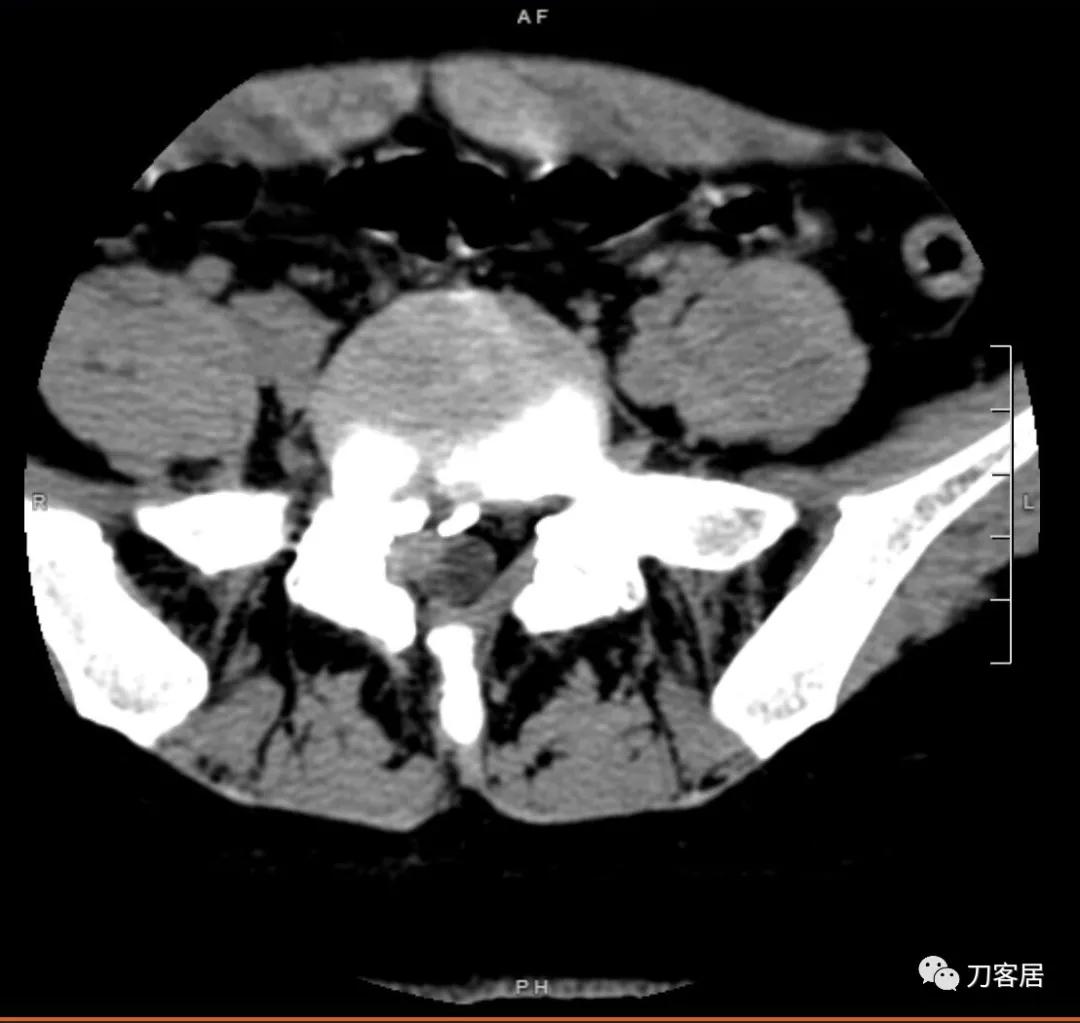

图3. 微创术前腰椎MRI横截面,提示腰5骶1椎间盘突出,右旁侧型,较大。右侧椎板似乎有缺损,应该是原来做过手术,减压所致的骨缺损。

图4. 微创术前腰椎MRI横截面,提示腰5骶1椎间盘突出,右旁侧型。

图6. 微创术前腰椎CT横截面扫描,提示腰5骶1椎间盘突出并骨化,且有曾经做过手术的痕迹。右侧椎板与棘突间的骨缺损以及骨化椎间盘间的骨缺损影。